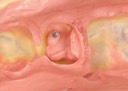

Alan Chinn #20 pre-op

Alan Chinn #20 caries removal